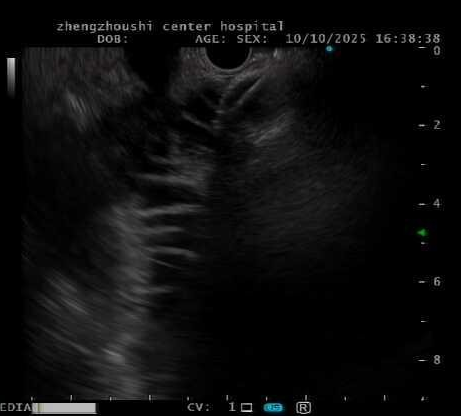

消化内科团队仔细研判影像,一个大胆而精巧的方案被提上日程:实施超声内镜引导下胃空肠吻合术(EUS-GE)。

“简单来说,我们不在‘堵点’硬撑,而是借助超声内镜的‘透视眼’,在胃里选定一个点,精准找到一段没有被肿瘤侵犯的空肠。”徐丽冬医生解释道。

“然后,我们在胃和这段健康的空肠之间,用一枚特殊的双蘑菇头支架,搭建一座绕过肿瘤的‘体内立交桥’。”

超声内镜探头如同高精度的“GPS导航”,在胃腔内实时扫描,清晰显示出肿瘤的边界、周围血管的搏动,以及最佳“桥墩”定位点。